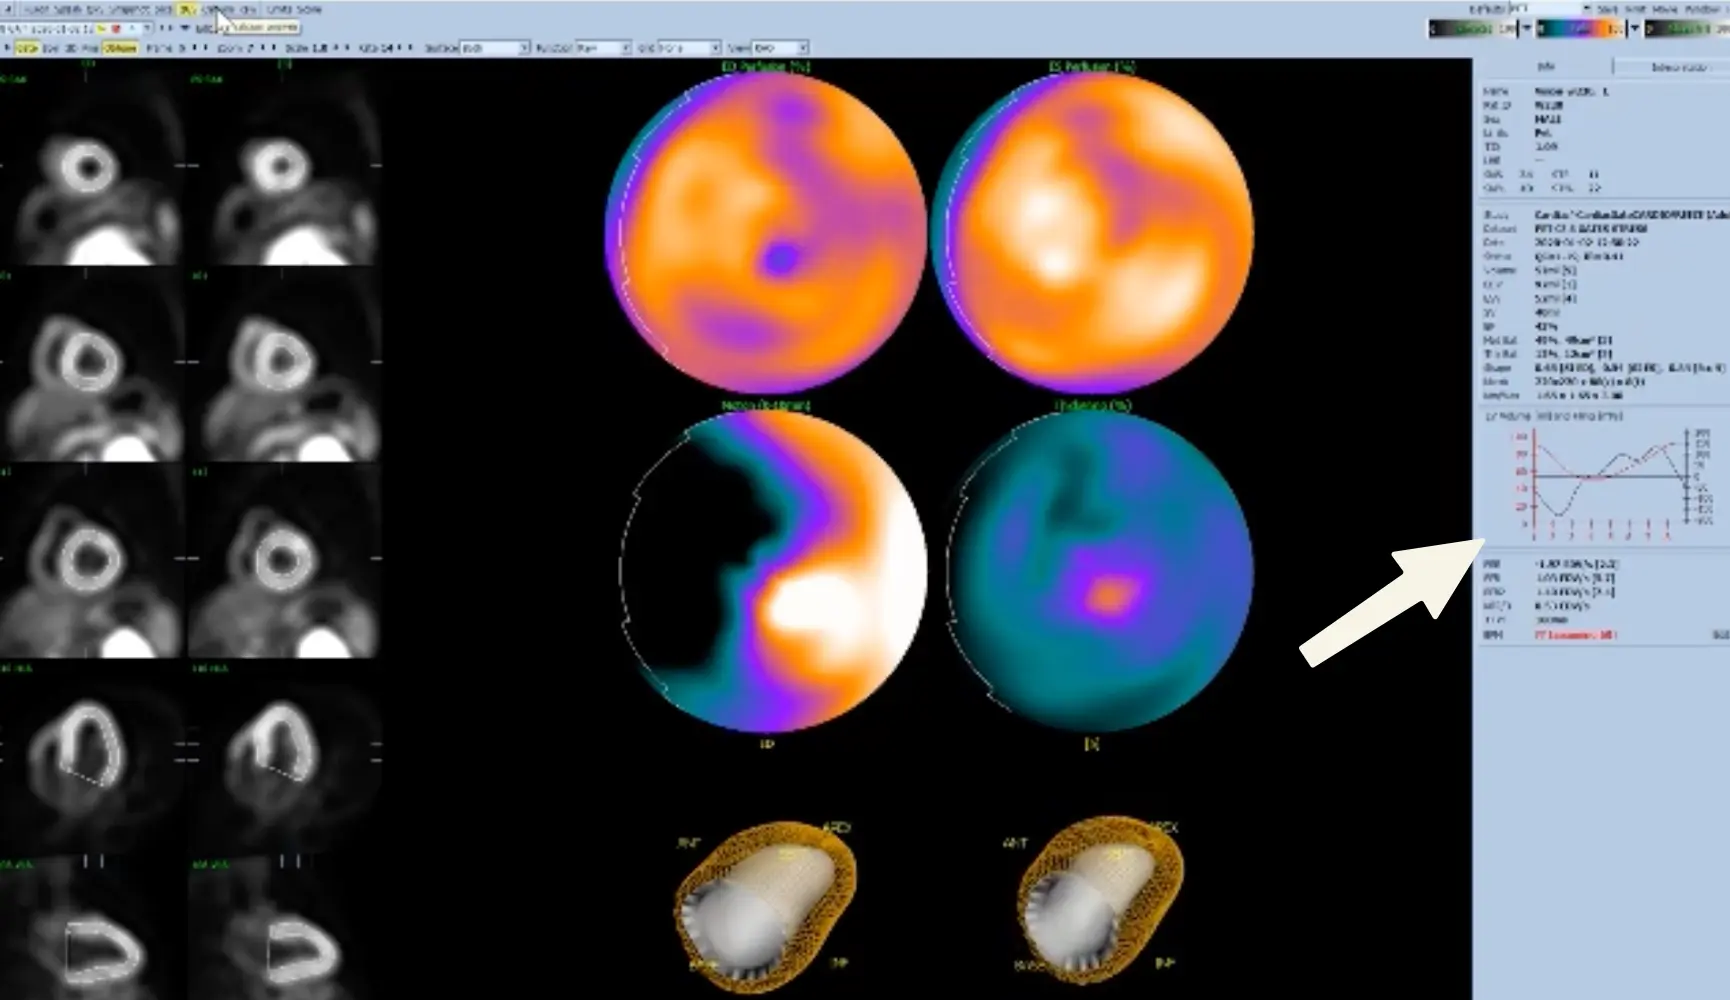

QGS

- Sanity check for EF estimation

- Look at the curve on the right

- The red line should be ‘V-shaped’ (makes sense as you go between diastole-systole-diastole).

- In reality, I’ve mostly seen it more U- than V-, but the point is that there should be a distinct trough/inflection point.

- As you can imagine, AFib can sometimes be finnicky.

- ⚠️ Data support that EF can be reported a little higher when using 16 vs 8 frames/second.